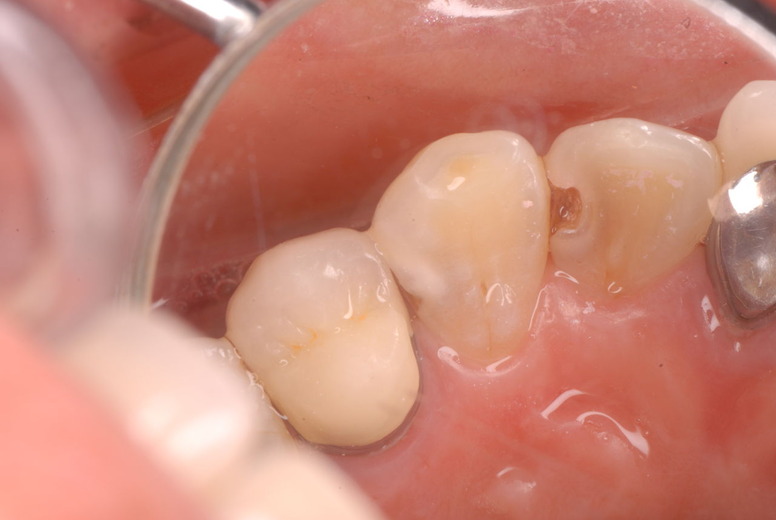

入れ歯の話から入りました。色々不満で注文があるようです。でも話が一段落して口腔内を調べると殆どの歯が重症で抜けそうな歯だらけなのです。

なぜ病気になるのかわからない方が多すぎます。歯が抜けるのは病気だからです。病気を治さずに何かお口の中に入れても土台である歯が抜けてしまっては同じことなのです。

何故歯が悪くなるのか、歯周病で抜けるのか分からなければ何を入れても歯は悪くなり抜けていくのです。

病気を治しましょう。それから差し歯や入れ歯を入れましょう!物を入れれば入れるほど、磨き方や掃除の仕方が上手にならなければ、すぐ抜けてくるのです。